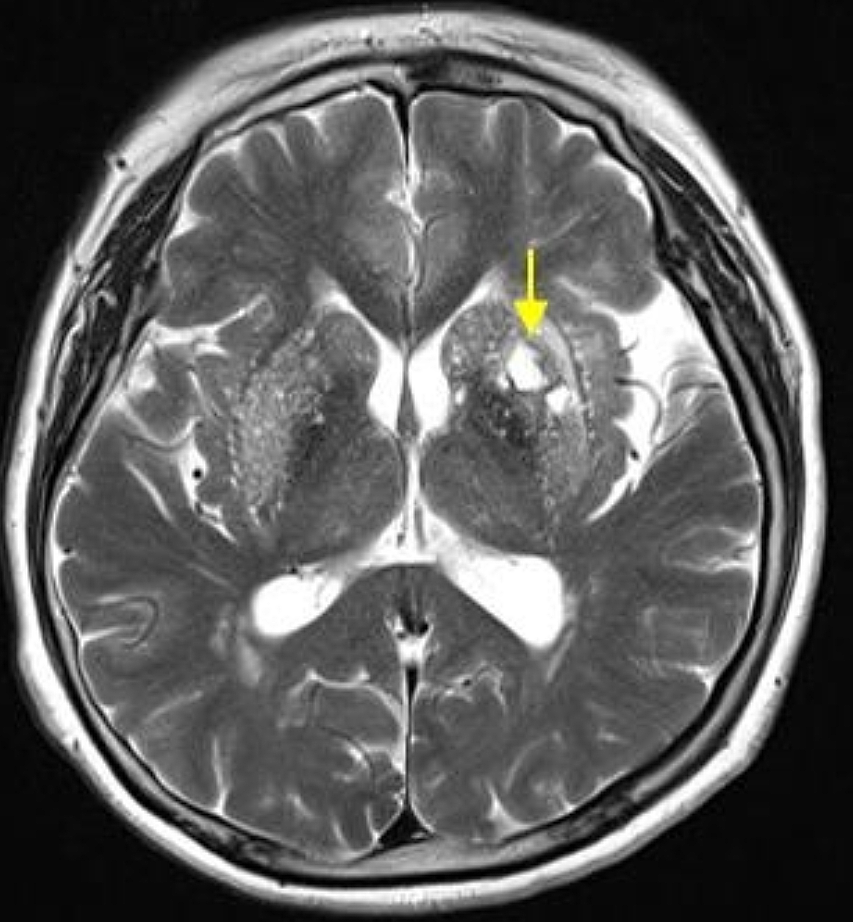

증상이 나타나면 검사를 통해 정확한 진단이 필요합니다. 보통 MRI, 경동맥 초음파 등을 통해 증상을 확인합니다. 뇌의 단층을 촬영하고 뇌혈류 검사와 뇌혈관조영술 등 여러 방법을 통해 질환을 확인합니다.